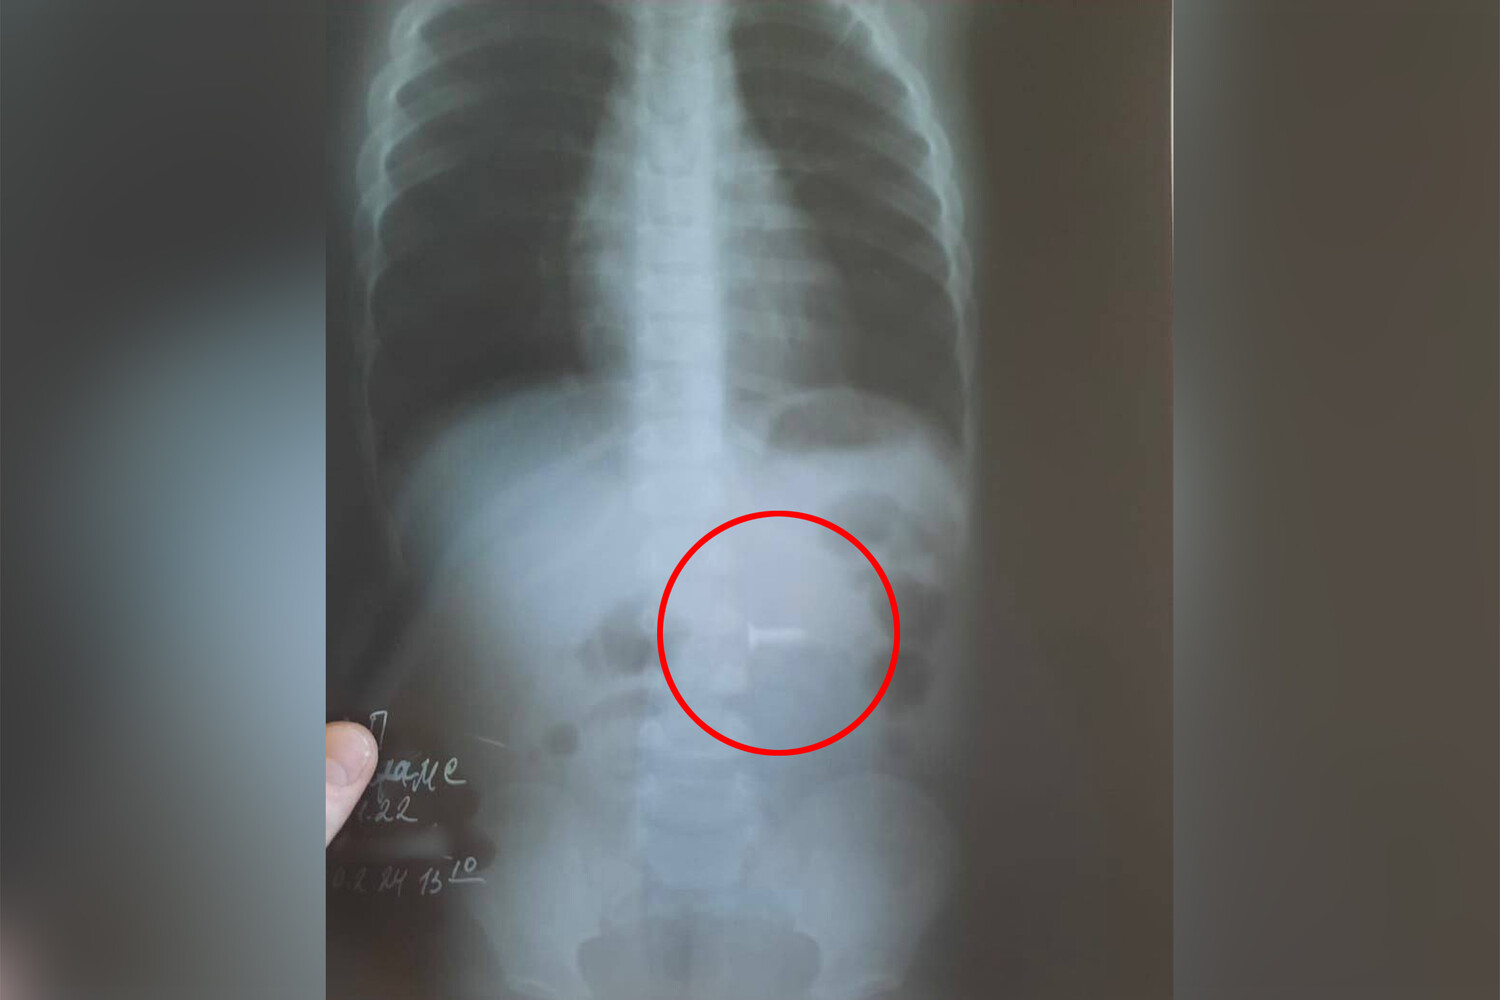

В Уфе годовалый ребенок проглотил саморез

В Башкирии врачи спасли ребенка с саморезом в желудке

В больнице скорой медицинской помощи Уфы врачи извлекли саморез из брюшной полости ребенка. Об этом сообщил министр здравоохранения Башкирии Айрат Рахматуллин.

В медицинское учреждение был доставлен годовалый ребенок с подозрением на инородное тело в желудке. По словам родителей, сын остался без присмотра, нашел в квартире саморез длиной полтора сантиметра и проглотил его.

В ходе обследования инородный предмет обнаружили в желудке, врачам удалось извлечь саморез из двенадцатиперстной кишки маленького пациента.